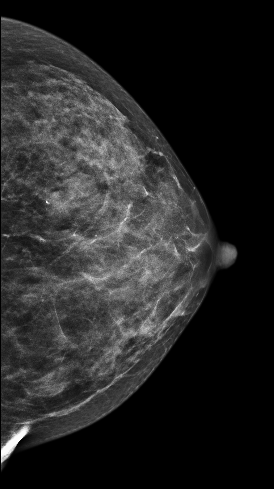

病史:患者,57岁,左乳乳腺癌术后,右乳发现肿块2月余。

V-preview图像:

在常规2D图像右乳外上象限隐约见一不规则团块影,部分边界模糊(容易漏掉),边缘可见粗大钙化灶,在V-Preview图像MLO位和CC位上团块显示较模糊,但钙化清晰可见,在3D-slab图像上我们可以清晰见到病灶呈分叶状改变,边缘可见蛋壳样钙化灶,周边见细线样透亮环。从以上细微征象我们可以初步判断是一良性病灶。

左乳外上不规则肿块,考虑良性病变,BI-RADS 3级。

病理证实左乳纤维腺瘤,此病例我们可以发现3D-Slab(厚层图像)对钙化灶形态大小显示更加清晰。